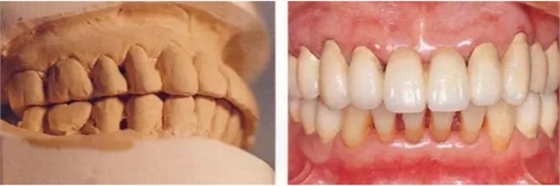

▲圖15-1,2

在正畸??漆t(yī)生處接受了正畸治療,雖然上頜正畸治療已經(jīng)完成,但由于磨牙區(qū)的邊緣嵴不整齊而導致牙體之間存在空隙。要想在這個狀態(tài)下護理牙周組織以及咬合狀況是非常困難的。由此可見,在治療時,正畸專科醫(yī)生與全科口腔醫(yī)生保持目標一致是非常重要的。